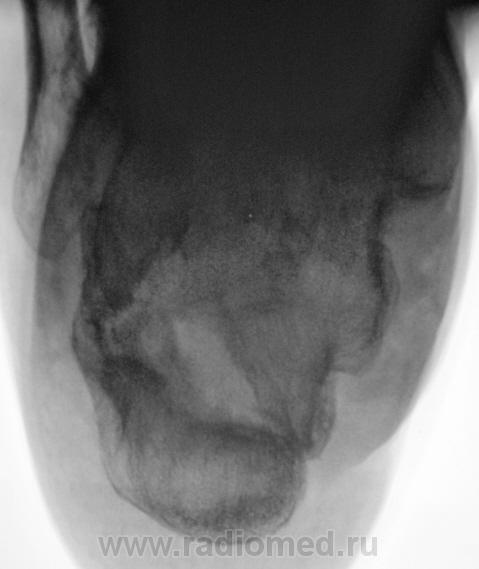

Пациент направлен на рентгенографию пяточных костей с диагнозом "остеомиелит". Год тому, пациент перенес перелом со значительным смещением отломков. Лечили... "как лечили". Сегодня прислали на рентгенографию с подозрением на остеомиелит.

Честно говоря интерпретировать такое не приходилось. Видно дефект кости и видно что он открывается за пределами кости. Так перелом сросся? Раз он как конь на параде, с чего тогда подозрение на остеомиелит?

В пяточной кости, определённо, не хватает костного фрагмента (может осколок удалён при операции); а в бугре пяточной кости - что-то "слишком светло" : как бы нейро-троф. расстройства

не спутать с лилизом (ОМ) - поднимать снимки п/е операции / снятия иммобилизации...

Пусть и дальше топает, как по мне - вариант комрессии с отличной консолидацией, а "псевдополость" - следствие этой самой компресии и оскольчатого перелома в сочетании с деформацией. Деструкции не видно!!!!!

А наружу ничего не открывается? ТИпа свищевого хода? На медиальной поверхности...

Ничего не открывается, да и пациент шагает, как конь "на параде".

Операции не было.

Видимо рассосался осколок. Только вот что за "дорожка" к наружной поверхности?

Операции не было. Был наложен ГИПС, и все...